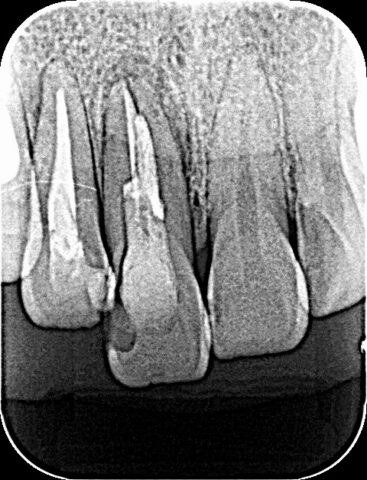

前歯インプラント

BEFORE

AFTER

症例情報

通院時の年齢

40代

性別

男性

通院目的

右上1の破折と右上2の審美障害

処置内容

右上1はインプラント補綴、右上2は補綴処置を行いました。

費用

約55万円

初診時

術中